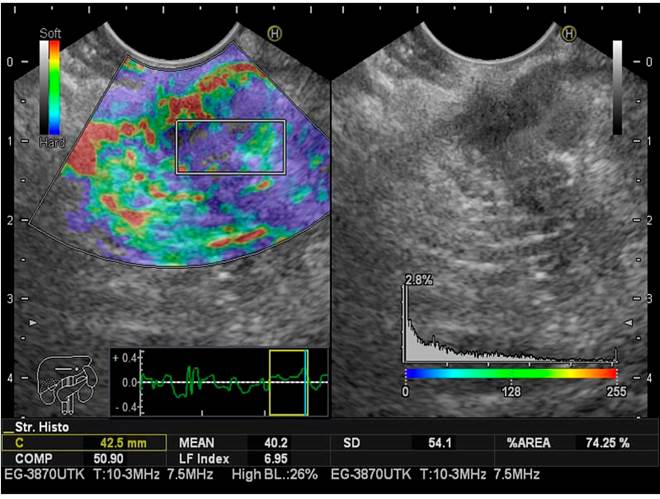

Para limitar el sesgo de selección, durante la ultrasonografía endoscópica se estimó tres veces, en todos los pacientes, el IFH tomado para el páncreas. El valor medio de las tres medidas se consideró el resultado final del análisis. Como ya se describió previamente, el IFH tiene en cuenta 11 parámetros que se utilizan para encontrar patrones de imágenes que evalúen la rigidez del parénquima hepático. Esto se logra con solo ubicar el cursor en el sitio donde queremos medir el IFH, al oprimir el botón “Enter” la computadora calcula inmediatamente este índice. Desde hace aproximadamente una década se usa en ecografía abdominal para la estatificación de la fibrosis hepática, usando imágenes de elastografía (RTE).

El IFH secuencial se logra de la siguiente manera:

Se convierte el área de análisis seleccionado de la imagen RTE en una imagen en escala de colores de 256 cuadros

Se traza el histograma de tensión

Se calcula la media de la tensión relativa (media), la desviación estándar de la tensión relativa (DE), la asimetría del histograma de deformación (SKEW) y la curtosis del histograma de deformación (KURT)

Se binariza la imagen RTE en regiones de blanco y negro: las blancas como de baja tensión (azul) y las negras como todas las demás regiones

Para caracterizar las regiones de baja tensión (azul) se calcula la proporción de regiones de baja tensión dentro del área de análisis seleccionada (% área), y la complejidad de la región de baja tensión (COMP)

Se calcula la entropía (ENT)

Se calcula el momento de diferencia inversa (IDM) y angular del segundo momento (ASM) para evaluar la textura de la imagen RTE

Se realiza un análisis de regresión múltiple para mejorar la precisión del diagnóstico, utilizando todas estas características de imagen, en lugar de diagnosticar con características de imagen individuales, como se muestra en la siguiente ecuación de regresión múltiple23:

IFH = -0,009 x MEAN - 0,005 x SD + 0,023 x % área + 0,025 x COMP + 0,775 x SKEW - 0,281 x KURT + 2,083 x ENT + 3,042 x IDM + 39,979 x ASM - 5,542

Este cálculo se realiza en milisegundos con el software, lo cual no aumenta significativamente el tiempo del procedimiento (Figuras 2,3y4).

El IFH para el páncreas (valor medio de las tres medidas), tomando los grados I y II como normales, y los grado III y IV como páncreas graso, fueron, respectivamente: normal (n = 34), IFH 2,60, rango de 0,97-3,47; páncreas graso (n = 21), IFH 3,87, rango 2-5,5. Con una prevalencia para páncreas graso de 38,18 %, cuando se realiza el IFH en tres subgrupos diferentes, considerados como ecoendoscópicamente normales, páncreas graso, pacientes con diagnóstico previo de cáncer de páncreas confirmado por histología. El IFH tomado en el páncreas fue para los tres grupos, respectivamente: normal (grado I y II): IFH 2,60, rango 0,97-3,47 (IC 95 % 2,17-3,02); páncreas graso (grado III y IV): IFH 3,87, rango 2-5,5 (IC 95% 3,44-4,29); cáncer de páncreas: IFH 6.35, rango 5,8-7,8 (IC 95% 5,92-6,77) (Tabla 4).